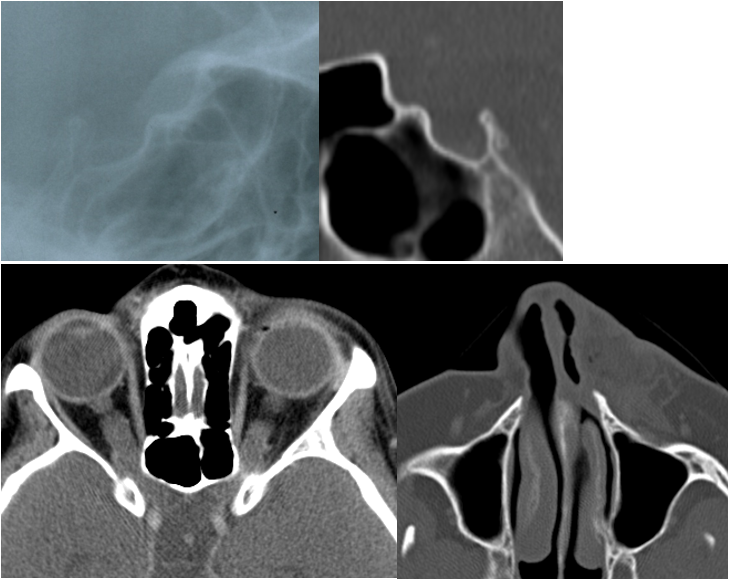

Figure 3: Radiographs of a NF1-affected individual with both OPG and PNF. Upper left side: Cropped image of lateral cephalogram of a NF1-affected 18 year-old female with bilateral OPG and j-shaped sella on lateral radiograph (anterior to the right). Upper right side: Computed tomography image illustrates sella turcica morphology: J-shaped sella on CT (anterior to the left). Sella area is in the range of normal values. Lower left side: Axial CT reveals bilateral enlarged optic nerves. Lower right side: This patient has a plexiform neurofibroma of the left nasal wing and adjacent cheek region.

Details of lateral radiographs of NF1 patients and control group illustrating sella turcica morphology are presented in Figure 3 [Fig. 3], Figure 4 [Fig. 4], Figure 5 [Fig. 5] and Figure 6 [Fig. 6].